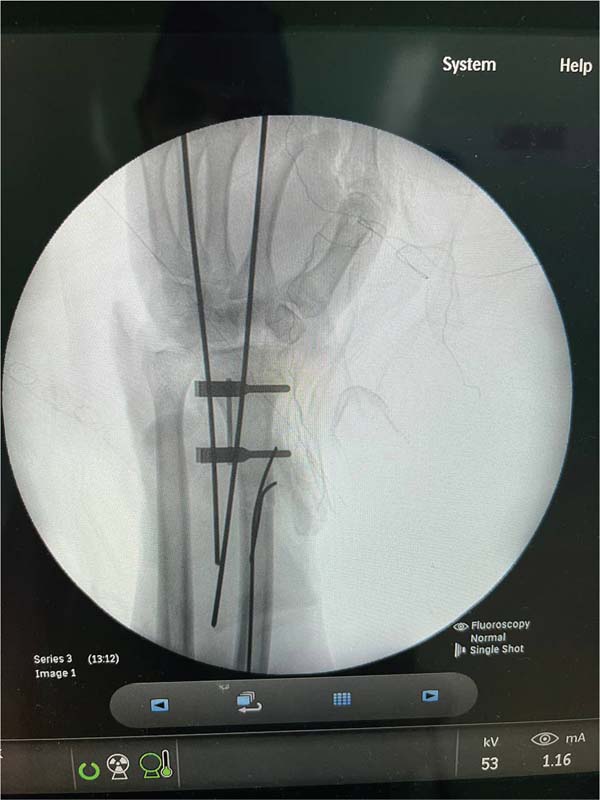

Após medidas iniciais de acordo com o protocolo Advanced Trauma Life Support (ATLS), foram realizados os seguintes tempos cirúrgicos: dissecção de cotos vasculares com identificação de artéria radial e ulnar, e nervo ulnar e mediano; heparinização dos vasos sanguíneos da extremidade amputada; fixação óssea do rádio e bloqueio do punho com fios de Kirschner; anastomoses microvasculares primárias da artéria radial e ulnar, assim como 3 veias dorsais; sutura de nervos mediano e ulnar com uso de microscópio; finalizando com tenorrafia em bloco dos flexores e enxertia de pele sobre ferimento devido a perda de substância (►Figs. 4-7).4